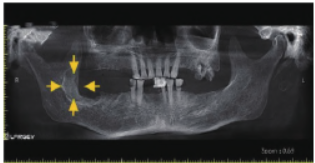

口腔曲面断层片(图1)示:右侧下颌升支前份可见一形状不规则的低密度影,边界不清晰,周围无骨白线,前至47牙根远中,后至右下颌升支中部,上至喙突下方,下至下牙槽神经管。口腔锥形束CT(cone beam CT,CBCT)矢状面(图2)示:右侧下颌升支内肿物侵犯骨质,可见大小不一多房间隔,颊、舌侧骨质不规则吸收缺如,边界欠清晰,并侵犯下牙槽神经管。

图2 术前影像学检查(CBCT 矢状面)。A. 下颌骨内占位;B. 不规则骨质破坏吸收;C. 颊、舌侧骨质破坏缺如并侵犯下牙槽神经管;D. 大小不一多房间隔。黄色箭头示病变处。